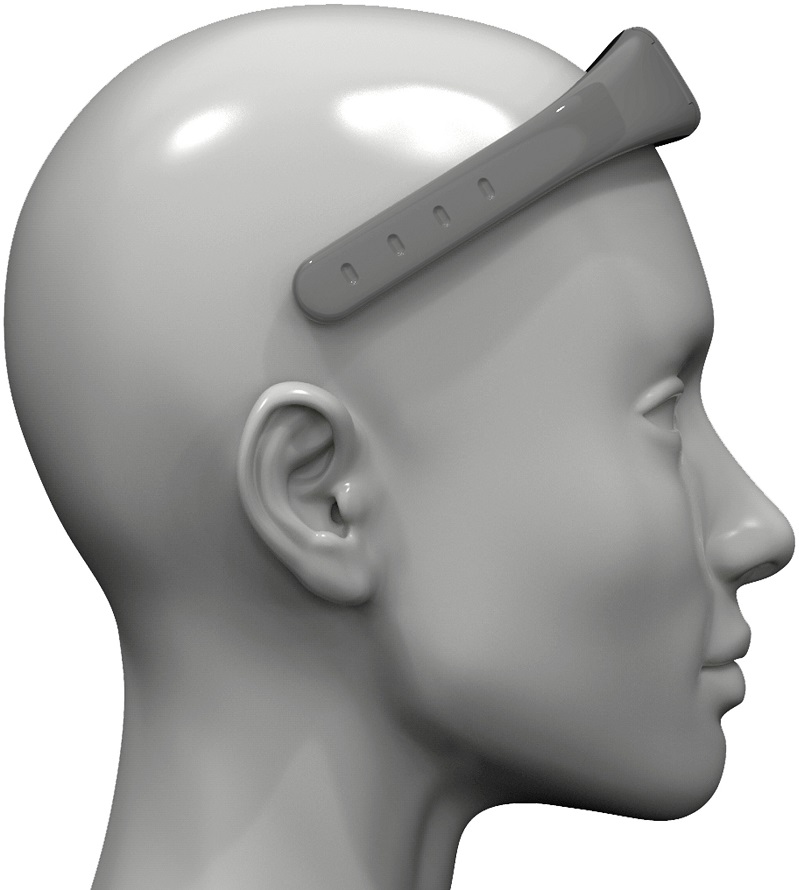

A partir do aplicativo, a Epistemic está desenvolvendo o Aurora, um aparelho no formato de um fone de ouvido esportivo que prevê crises epilépticas. O equipamento conta com uma novidade, que são eletrodos secos (sem a necessidade de usar substâncias pastosas, como é comum em hospitais), que produzem um eletroencefalograma e, diante de alguma variação que indique a possibilidade de crise, é enviado um alerta a paciente e cuidadores e familiares autorizados.

“Pelo formato, o Aurora é indicado para ser utilizado atrás da cabeça durante o dia e na testa à noite, para não atrapalhar o sono e o posicionamento no travesseiro. Ainda passa por testes clínicos para ir ao mercado, mas já apresenta resultados positivos. O Epistemic App desenvolvido no Samsung Creative Startups tinha avanços, como a possibilidade de se registrar uma crise com um simples clique no raio no canto superior direito da tela inicial, além de oferecer dicas nutricionais de profissionais especializados e as melhores opções no momento de agir diante de uma crise. O Aurora é uma evolução nesse auxílio ao controle de epilepsia”, explicou Paula Gomez, CEO da Epistemic.